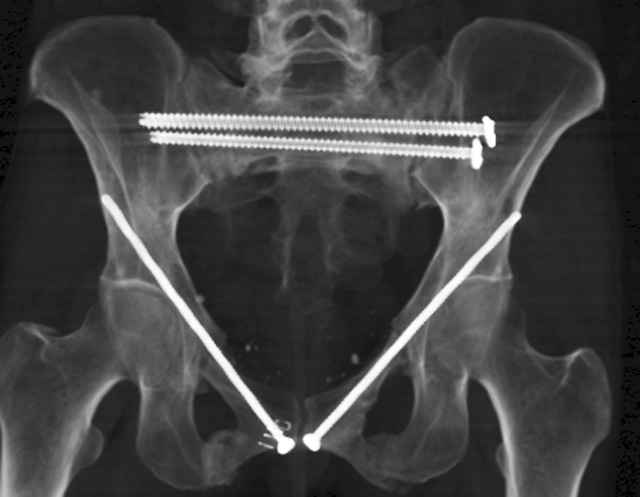

Here are a recent patient’s example slides...

54 yo Female Fell c/o Pain

Initial Films

?Instability on Exam - Limited by Pain

NonOp Initial Mgmt

3 Months After Fall

Continued Pain & Immobility

(+) Instability to Compressive Manual Exam

Pelvic CT Scan - 3 Months After Fall

Sacral Injuries

Ramus Fractures

Percutaneous Fixation

(B) Ramus-Retrograde

2 TransIliac-TransSacral

Upper Segment